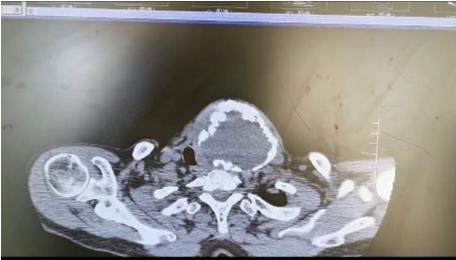

患者朱女士,68歲,頸部包塊呈進(jìn)行性增大50年,來院后彩超及CT提示左側(cè)甲狀腺腫瘤已經(jīng)超過10公分并邊緣鈣化,氣管移位較明顯,腫瘤較大屬于罕見,不僅給患者造成心理陰影,還影響了正常生活,偶有憋悶不適,進(jìn)食較大食物感哽咽不適。流動醫(yī)院下鄉(xiāng)義診時(shí),發(fā)現(xiàn)包塊已經(jīng)很大了,影響到頸部的活動及飲食。醫(yī)生與患者及家屬溝通講解病情,表示我們?nèi)揍t(yī)院能治療。最后患者及家屬抱著試一試的態(tài)度來到延安大學(xué)咸陽醫(yī)院。

因逐漸長大的頸部嚴(yán)重影響飲食及活動,長達(dá)50年的折磨,患者身體很瘦、體質(zhì)差。甲狀腺腫瘤,瘤體大,手術(shù)創(chuàng)面較大,損傷喉返神經(jīng)及甲狀旁腺風(fēng)險(xiǎn)高,術(shù)后可能出現(xiàn)聲音嘶啞及低鈣抽搐等嚴(yán)重并發(fā)癥。同時(shí)瘤體長期對氣管的壓迫,致術(shù)后可能出現(xiàn)氣管軟化而發(fā)生致命性并發(fā)癥。